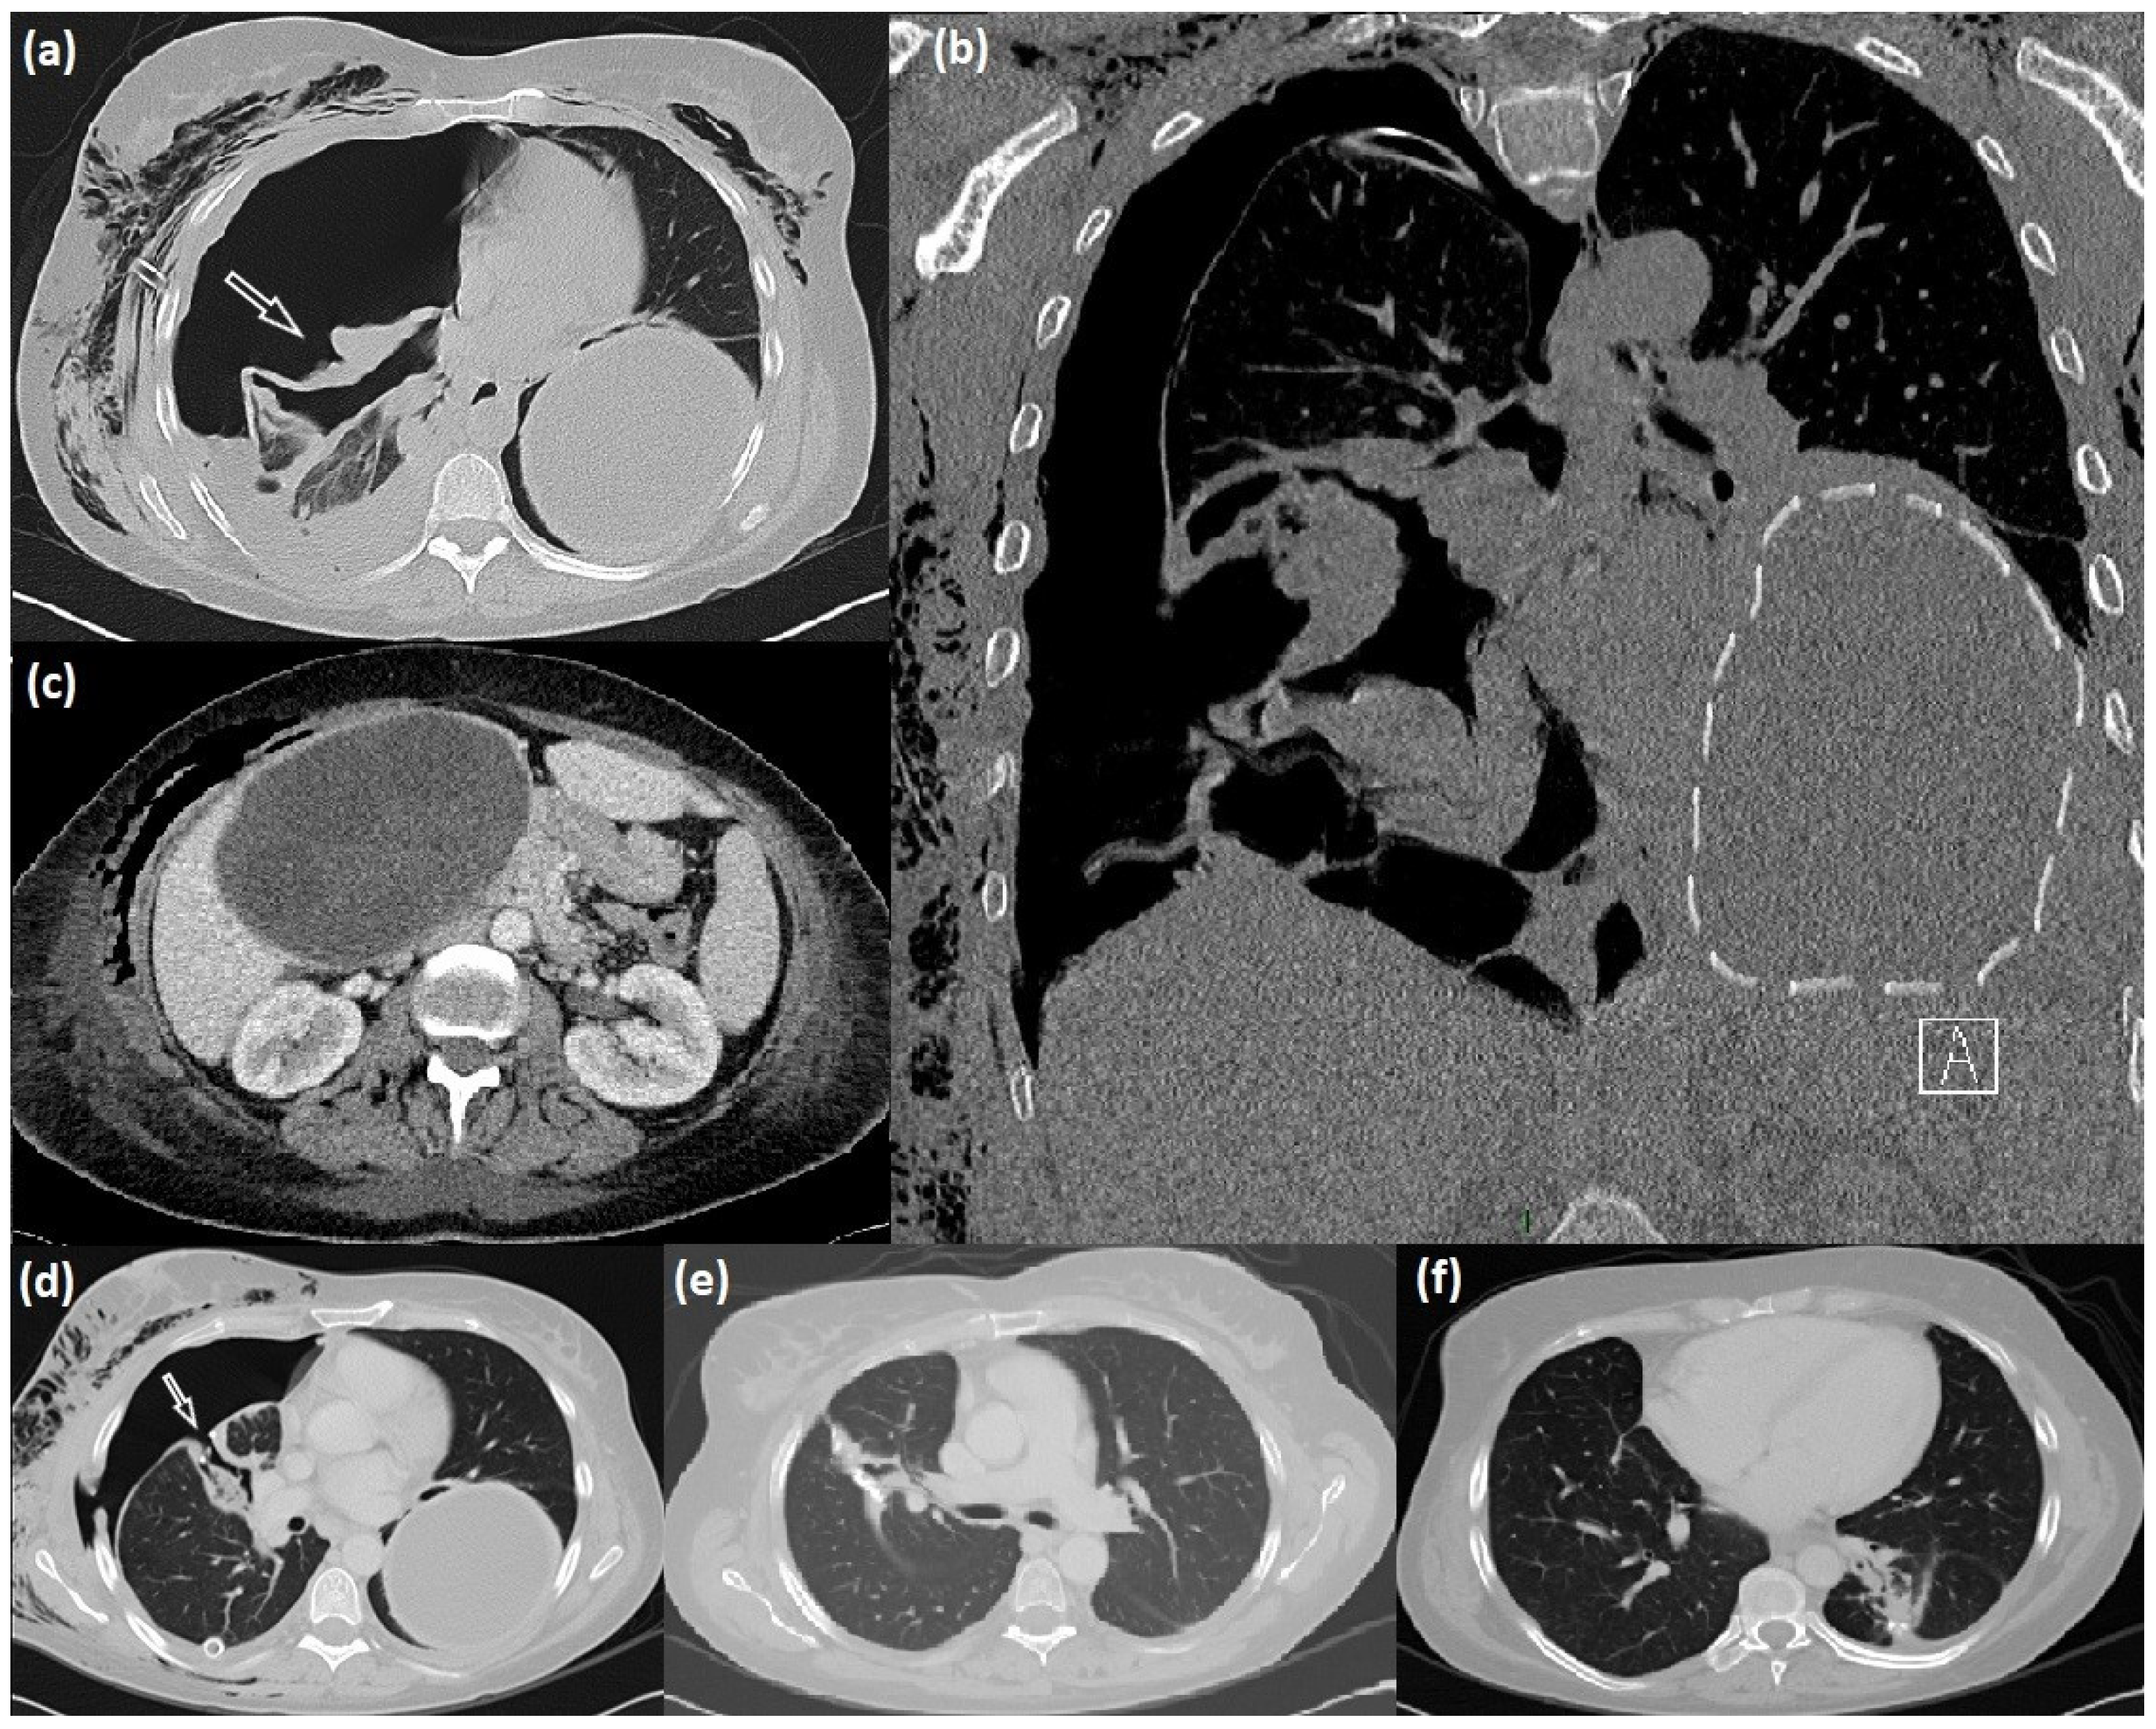

2. Case Description